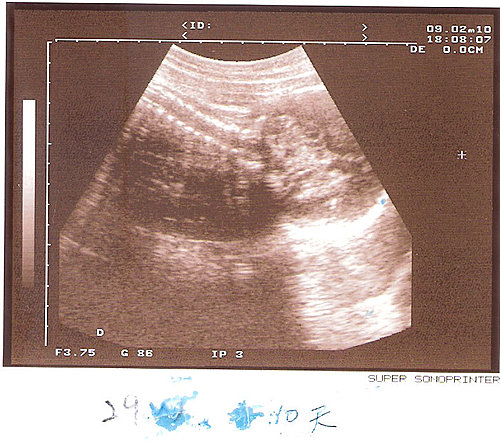

之前在婦幼做自費高層次超音波時,檢驗師有開4D影像,那個清析度真的有別於一般的2D超音波,不過,畢竟是高層次的檢查為主,所以4D影像不多;牛大人之後就非常堅持要自費去照4D,滿足他想看看女兒的傻爸爸心態。

上網大致看了一下哪裏可以做,發覺中山醫院附屬的杏群診所評價還滿不錯的,反正照4D只是純觀賞娛樂用,可以讓我們先看到小櫻桃的面容,這點還真令人期待,不過,照個4D要花3000元,也還真是不便宜,所以在照4D的前一天,我可是跟小櫻桃溝通了幾次,要她配合檢驗師的話,把臉抬起來,讓我們看清楚她的臉啊!

本來是希望晚一點再照,但杏群的預約實在排得太滿了,只能說這年頭父母都急著想先看肚裏的寶貝是否安好?或長得如何? 不管花多少錢,現在的父母還真都覺得值得呢! 由於我預約時間較晚,還好有卡到一個過年前的時段,雖然我覺得那時週數還沒有很大-約27.28週,不過,也只有這個時間有空可以被安排進去了。

當天到杏群診所時,先在一樓櫃枱處進行報到及繳費,然後就有人帶我到樓上等候;這次我掛的是舒老師的診,可能前一個孕婦的寶寶沒有配合,所以照的時間就拖了好久,我們也等了好一會,杏群在前一天會提醒孕婦可以在照的前三十分鐘先喝冬瓜茶,讓寶寶可以比較活躍,不過我不喜歡冬瓜茶,所以我改喝比菲多,反正只要是甜的,我的小櫻桃應該都很喜歡吧!

終於輪到我們了,走進超音波室,感覺是滿柔和、不冰冷的空間,而且舒老師人滿好的、也滿和靄的,連超音波的冷凝膠都是溫熱的,不像一般產檢時是冰冷的,就這點來說,杏群還滿貼心的。

之前在婦幼做自費高層次超音波時,檢驗師有開4D影像,那個清析度真的有別於一般的2D超音波,不過,畢竟是高層次的檢查為主,所以4D影像不多;牛大人之後就非常堅持要自費去照4D,滿足他想看看女兒的傻爸爸心態。

之前在婦幼做自費高層次超音波時,檢驗師有開4D影像,那個清析度真的有別於一般的2D超音波,不過,畢竟是高層次的檢查為主,所以4D影像不多;牛大人之後就非常堅持要自費去照4D,滿足他想看看女兒的傻爸爸心態。